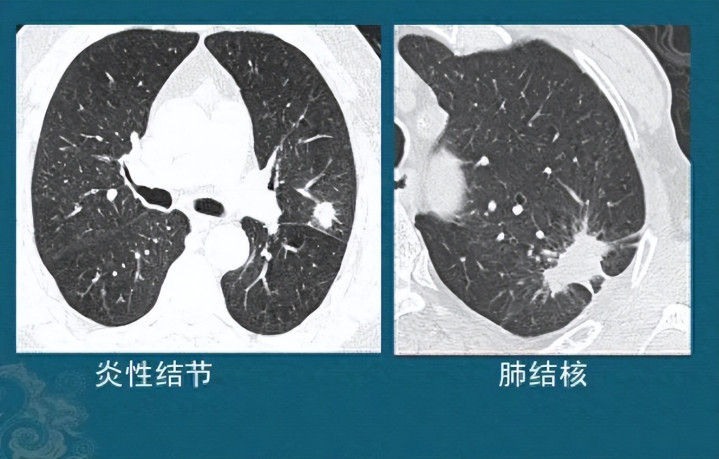

猫爪草擅长"搜剔"肺中痰火,与夏枯草构成"黄金拍档"。临床常见肺结节患者服药后,CT走漏病灶显著接纳。